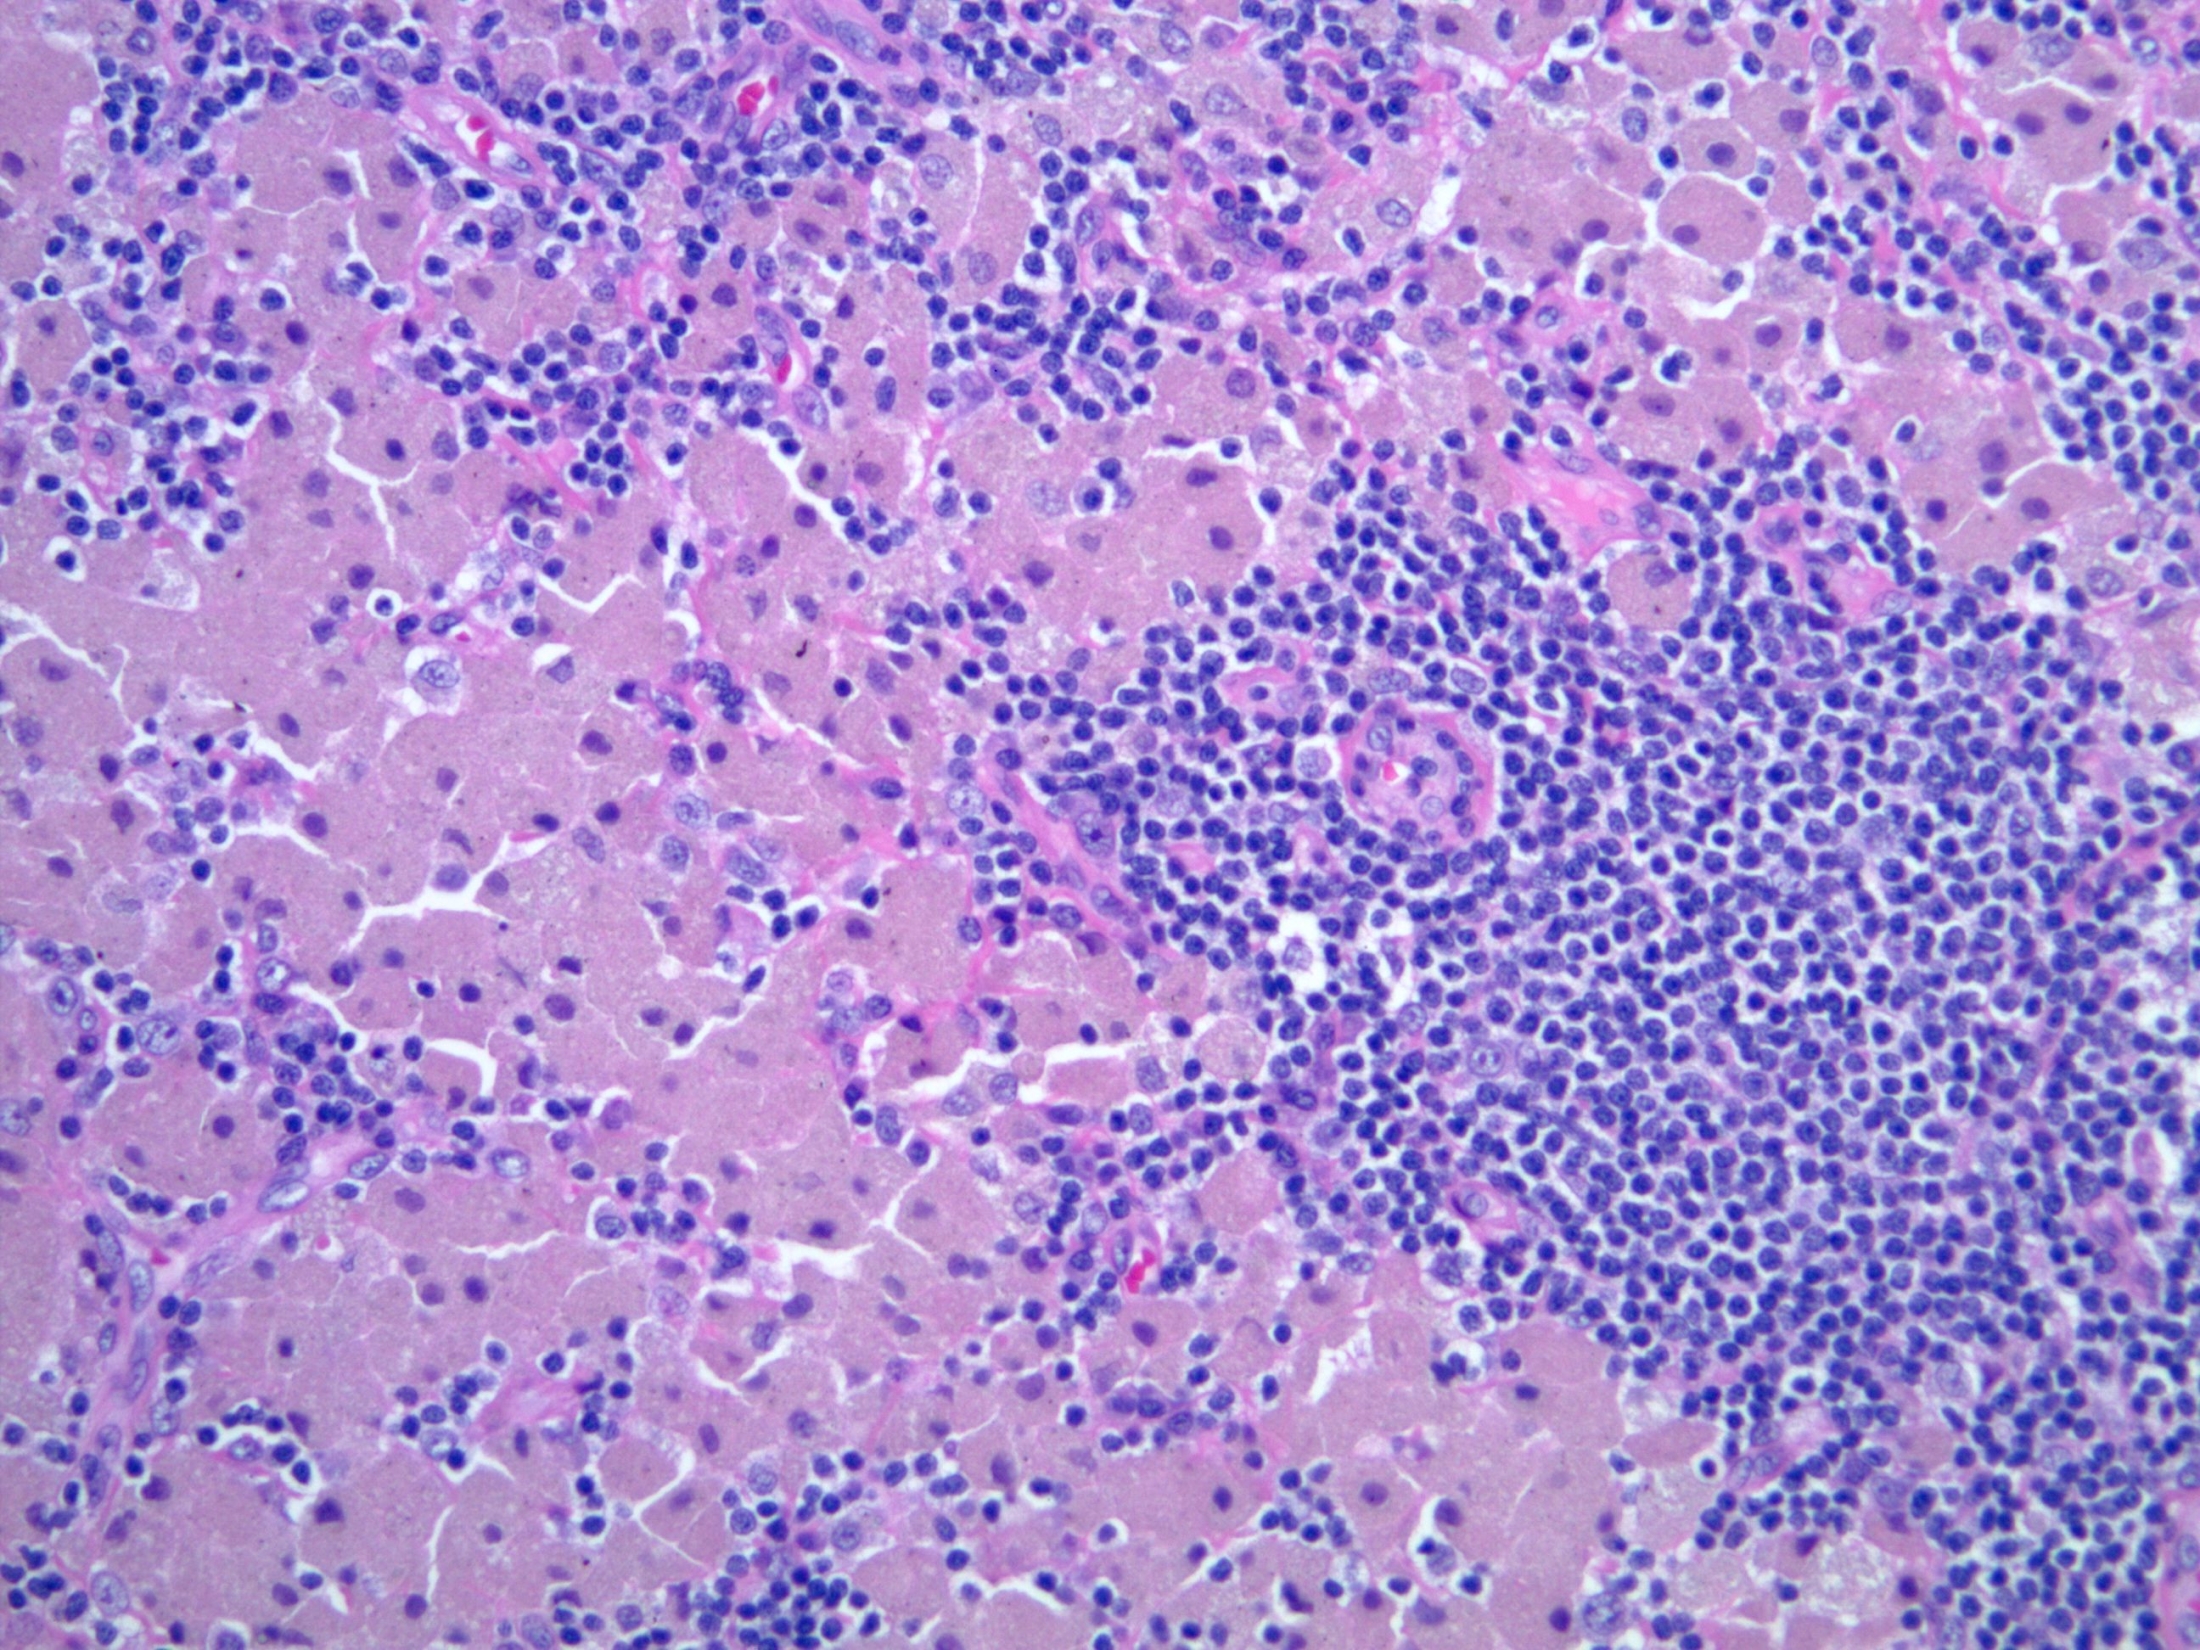

T cell lymphoma

T cell lymphoma 97 фото